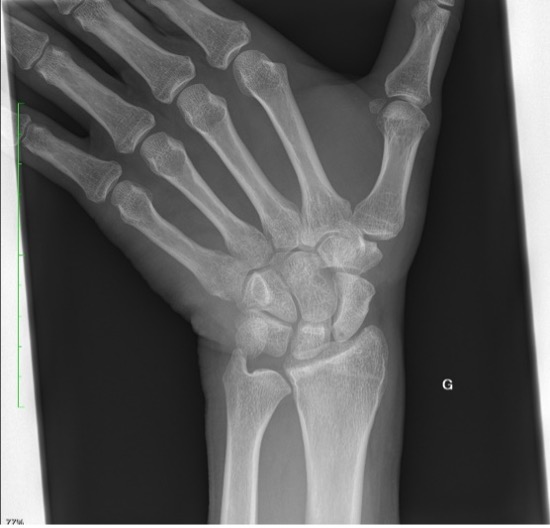

Un patient se présente pour des douleurs au niveau du poignet gauche, suite à une chute à vélo avec réception sur la paume de la main. Cliniquement, nous observons un œdème au niveau du dos de la main, des douleurs à la mobilisation du poignet avec une discrète limitation de l’extension et une prono-supination conservée.

La radiographie effectuée révèle une fracture du triquétrum. Les fractures du triquétrum (ou os pyramidal) sont les fractures du poignet les plus fréquentes après celles du scaphoïde, représentant 13% des fractures des os du carpe. Elles résultent habituellement d’une chute sur la main en hyperextension et déviation ulnaire. Elle est fréquemment retrouvée chez des pratiquant·es de sports de combat.

Il existe trois types de fractures du triquetrum : les fractures corticales dorsales, les fractures du corps et les fractures corticales palmaires. Pour ce patient, il s’agit d’une fracture de type 1 (95% des cas), qui est une fracture par avulsion associée à des lésions des ligaments dorsaux du carpe et considérée comme une « entorse grave du poignet ».

Les fractures corticales dorsales sont les plus courantes et sont généralement bénignes, tandis que les fractures corticales palmaires sont les moins courantes et peuvent poser des problèmes.

La clinique est aspécifique mais le diagnostic doit être évoqué face à des douleurs sur le côté ulnaire du carpe, après une chute main en extension. Les fractures du triquetrum passent facilement inaperçues sur les radiographies conventionnelles du poignet, mais elles sont souvent associées à des lésions ligamentaires importantes conduisant à une instabilité du carpe, ou évoluent vers une pseudarthrose. Un complément par CT (ou IRM) peut être nécessaire afin de confirmer le diagnostic et préciser les lésions.